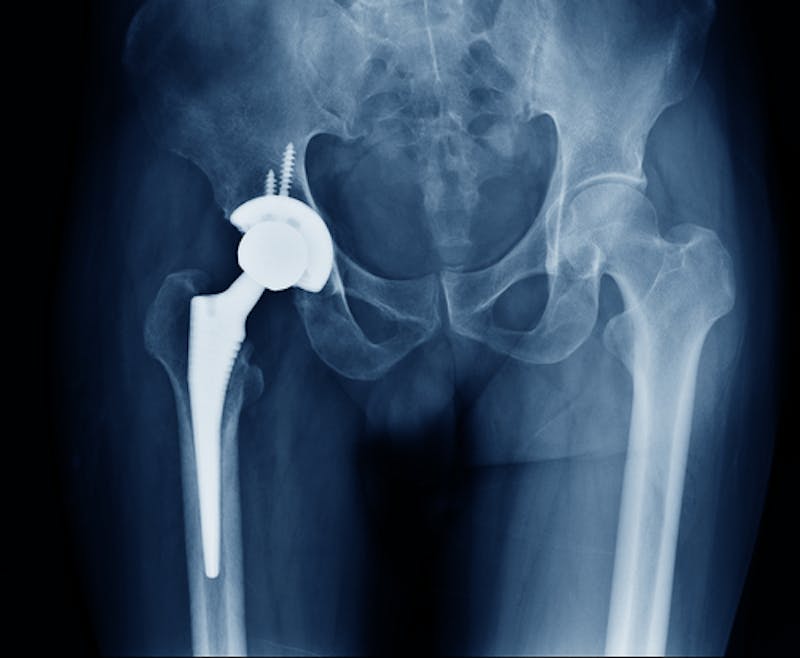

What is the Exactech hip Device that has been Recalled?

The Agency for Healthcare Research and Quality reports that surgeons in the United States perform more than 450,000 hip replacements every year. Patients who begin to experience hip pain that affects their everyday life can benefit from hip replacement surgery. Still, there is a ...